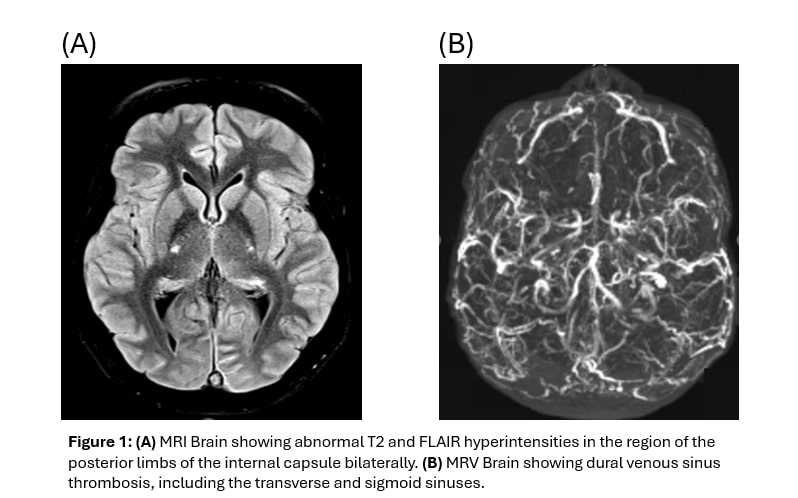

Conclusion: This study underscores the complex and challenging nature of pBD, with nearly a quarter of patients developing neurologic manifestations, indicating a higher burden of severe disease than traditionally recognized. The substantial diagnostic delay of almost three years, despite 80% initially presenting with oral ulcers, represents a modifiable gap in care that may contribute to progression toward major organ involvement. Improving prognosis in pBD, particularly for those at risk of Neuro-Behçet requires heightened clinical suspicion, earlier referral, systematic neurologic screening, and neuroimaging in high-risk patients. Timely escalation to targeted immunosuppressive and biologic therapy within coordinated multidisciplinary care pathways is essential for optimizing patient outcomes.